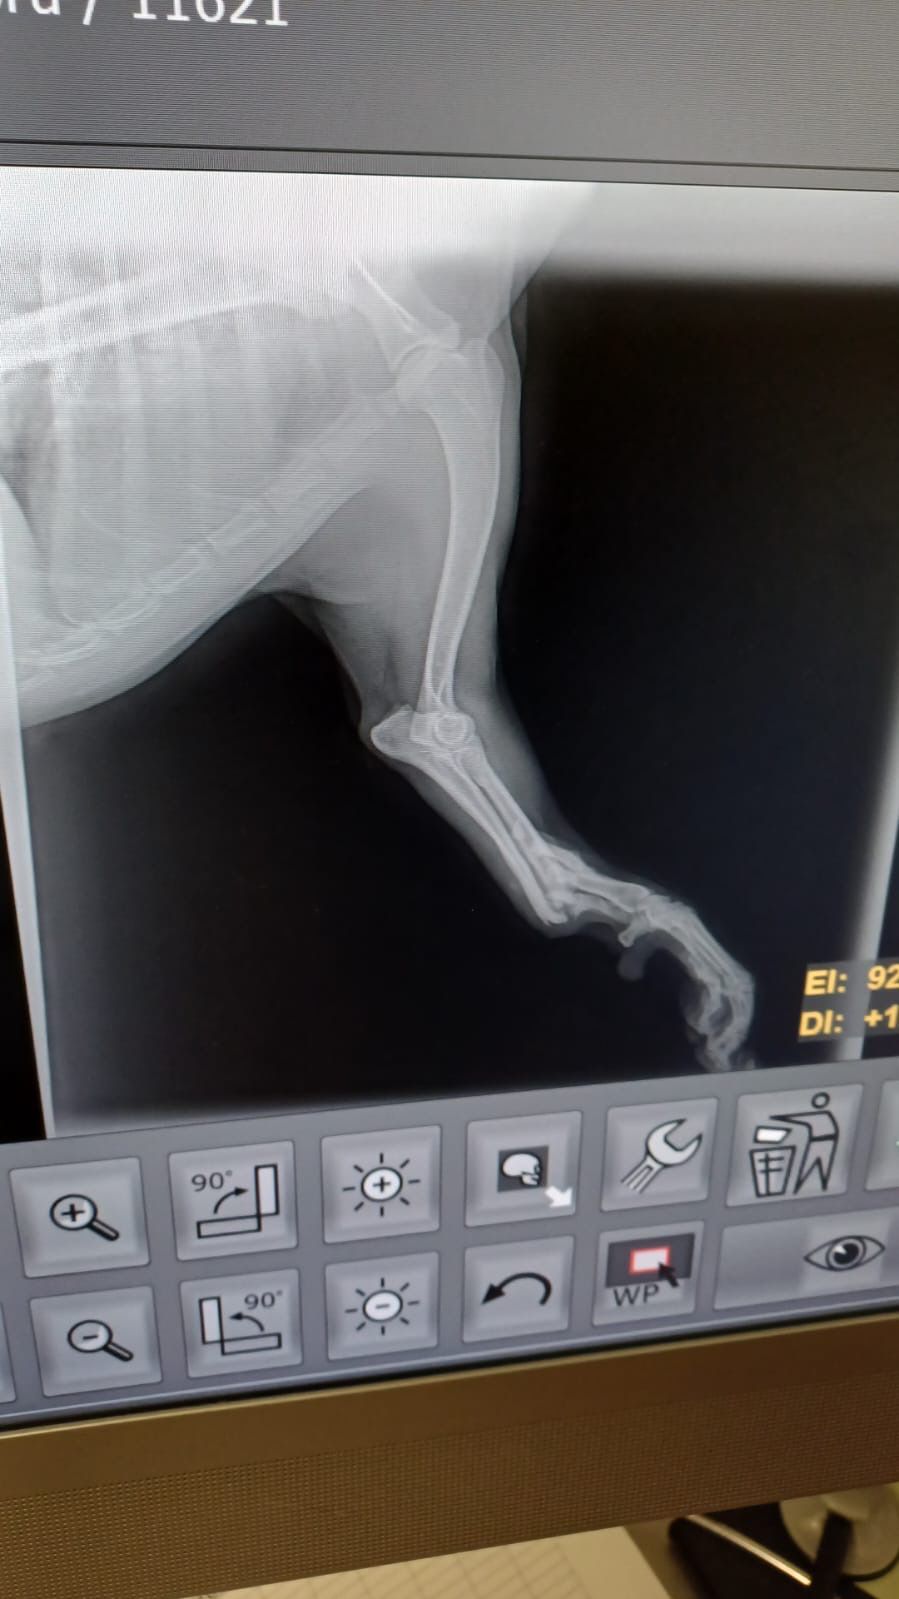

Leider stimmt etwas mit seiner linken Vorderpforte nicht, mit dieser humpelt er und wenn er sie aufsetzt, ist sie völlig durchtrittig und wirkt sehr instabil. Möglicherweise liegt hier eine (ältere) Verletzung vor.

linkes Vorderbein wurde amputiert

| zur Besonderheit: | linkes Vorderbein amputiert |